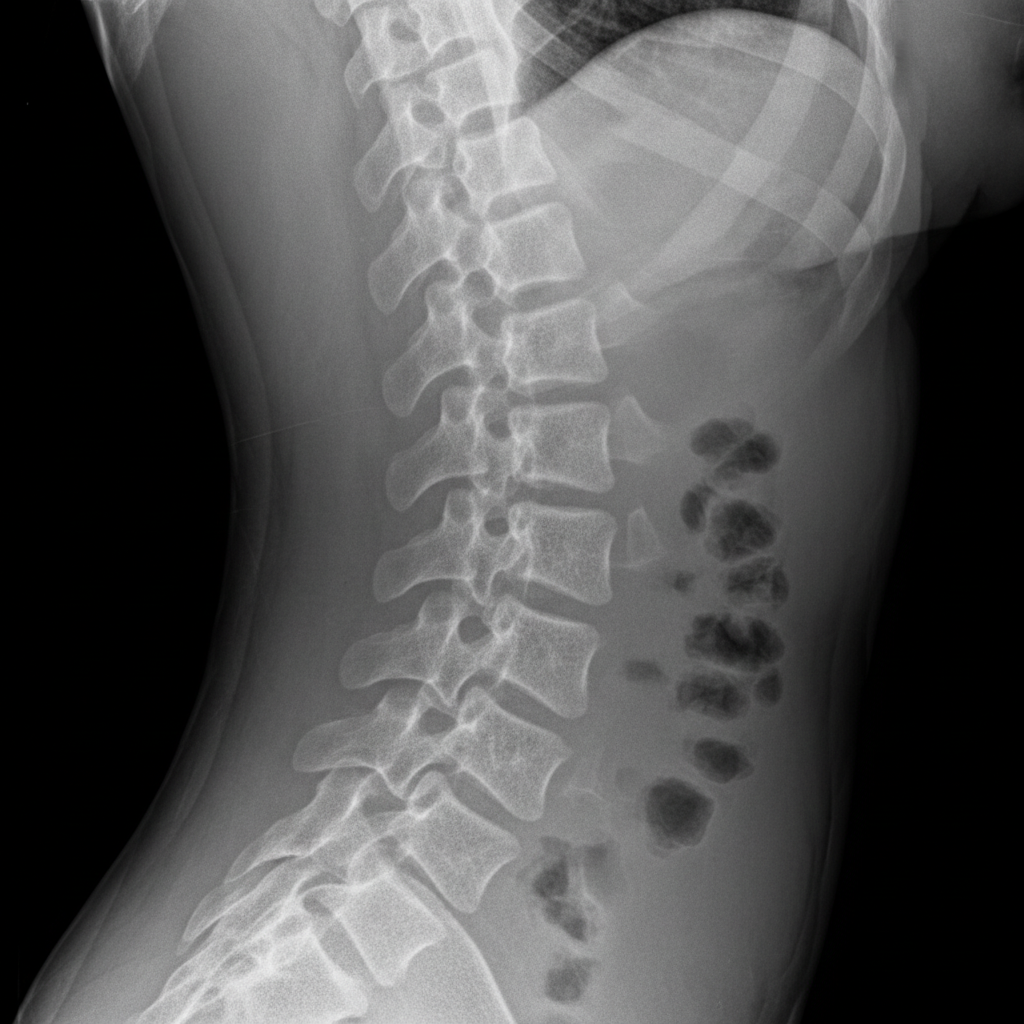

Q: 후유장해 평가를 위해 어떤 서류나 준비물이 필요할까요?

A: 가장 중요한 건 그동안의 모든 의료 기록이에요. 사고 경위를 담은 진료 기록, X-ray, CT, MRI 같은 영상 검사 자료, 수술 기록 등이 모두 필요하답니다. 이런 자료들을 바탕으로 의사 선생님이 장해를 평가하고 진단서를 작성해주실 거예요. 모든 기록을 꼼꼼하게 보관하는 습관이 정말 중요해요.